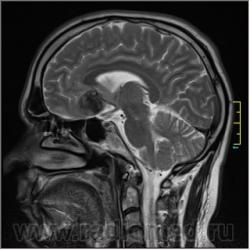

Пациентка направлена на исследование с диагнозом "Гипертонический криз", энцефалопатия неуточненная.

Sag T2:

частично функционирующая аневризма

Иначе говоря, аневризма с хронической геморрагией, т.к. мы видим фракции крови различного возраста.

По-моему, аневризма с пристеночными тромбами.

Постепенное пристеночное образование тромбов приводит к появлению типичного для аневризмы феномена -слоистости МР сигнала в полости аневризмы. Данная картина демонстрирует слоистый характер тромботических масс в полости аневризмы .Функционрирующая часть имеет низкий сигнал во всех режимах сканирования. Дополнительно-перифокальный отек.

А может более корректно интерпретировать как частично тромбированная аневризма... Уж коь речь идет о фракциях, ну то есть о тромбе по сути.... Ну и плюс перфокальный отек головного мозга (вероятнее цитотоксический+вазогенный).